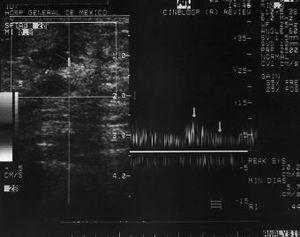

La mastografía mostró una imagen ovalada, densa, con márgenes irregulares en el CSE izquierdo. El diagnóstico fue de lesión sospechosa de malignidad, categoría 4, según el Colegio Americano de Radiología.8 (Fig. 1). En el US la lesión se localizaba entre las 1 y 2 horas de la línea B del radio del reloj, hipoecoica, de márgenes irregulares, de 2,3 * 2 cm en los diámetros anteroposterior y transverso, respectivamente. El estudio Doppler color mostró índices de baja resistencia: 0,44 a 0,48 (Fig. 2). En el gammagrama con sestamibi marcado con tecnecio-99 se observó captación intensa en el sitio de la lesión (Fig. 3). El reporte de la biopsia por aspiración con aguja fina (BAAF) fue de mastitis crónica granulomatosa. La prueba subdérmica de tuberculina fue negativa. En la biopsia incisional se demostraron bacilos ácido alcohol resistentes (BAAR) con la técnica de Zhiel Neelsen y el cultivo del tejido en el medio de Lowenstein-Jensen fue negativo. Para investigar otro foco de Tb se realizó telerradiografía de tórax, la cual fue normal, y además pruebas serológicas como la prueba de ensayo de inmunoabsorbencia de enzimas conjugadas (ELISA) y la prueba de reacción en cadena de polimerasa (PCR), siendo ambas negativas. El tratamiento con isoniacida, rifampicina y pirazinamida a los 3 meses de haberse iniciado causó remisión clínica y los estudios de imagen fueron normales. La paciente continuó el esquema terapéutico hasta completar 6 meses.

Fig. 2. US mamario Doppler color. Lesión vascularizada con índices de baja resistencia.